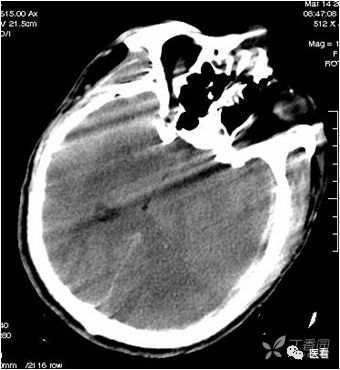

有躁动、呼吸运动和非自主运动(心跳、胃肠道蠕动)所致的伪影。

本例因为躁动明显,产生的伪影显著、杂乱。